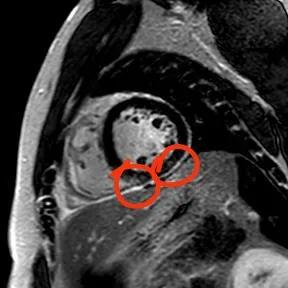

“快!做磁共振觀察心肌有無受損及程度。”影像診療中心陳寶瑩副主任為小燁進(jìn)行心臟磁共振平掃及增強(qiáng)掃描。結(jié)果提示:患者有急性心肌損傷,考慮心肌梗死。結(jié)果驗(yàn)證了小燁的心肌大片區(qū)失活。

方向比努力更重要,對(duì)于醫(yī)生而言更是如此,準(zhǔn)確把握病因方向,才能有效治療。心臟磁共振,成為非侵入性診斷心肌疾病的金標(biāo)準(zhǔn),能準(zhǔn)確地鑒別心肌炎、應(yīng)激性心肌病、心肌病淀粉樣變性、擴(kuò)張性心肌病及心肌梗死等,并能對(duì)心肌梗死后心肌纖維化進(jìn)行定量評(píng)估。